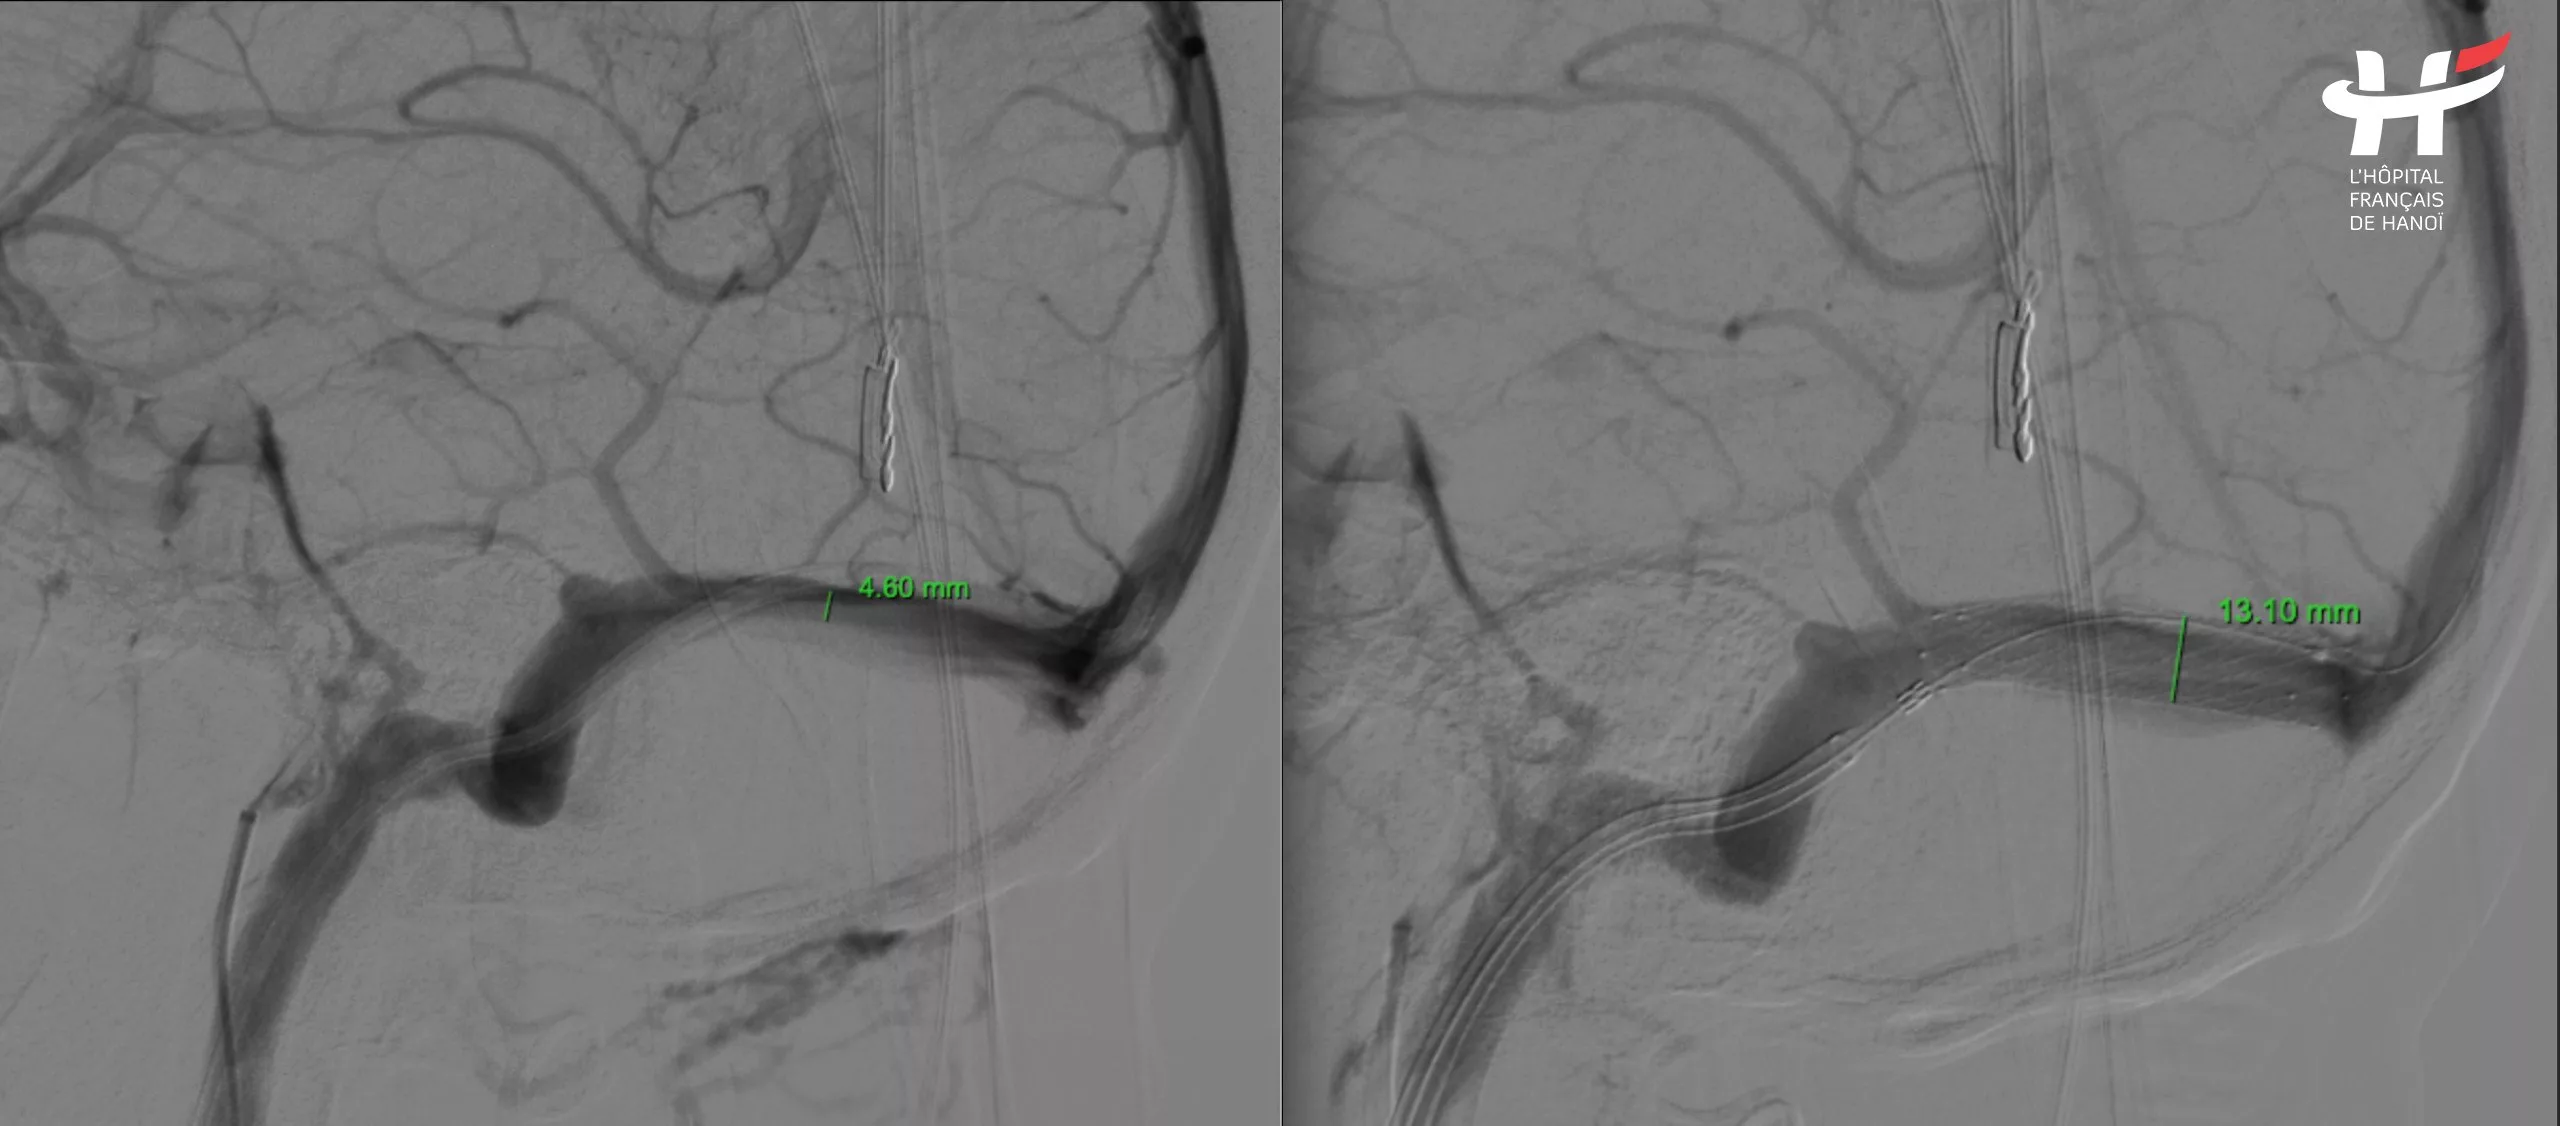

Sau khi tham khảo ý kiến cùng các chuyên gia về can thiệp mạch máu, các bác sĩ đã kết luận bệnh nhân bị hẹp xoang tĩnh mạch ngang bên phải, một tĩnh mạch lớn nằm trong não. Đây có thể là nguyên nhân gây nên mọi đau khổ của bệnh nhân trong nhiều năm qua. Điều đáng mừng là đây là một căn bệnh có thể điều trị được.

Sau khi thống nhất, các chuyên gia đưa ra quyết định cuối cùng là đặt stent xoang tĩnh mạch ngang bên phải cho bệnh nhân để giải phóng phần bị tắc hẹp giúp máu lưu thông bình thường.

Theo TS.BS Nguyễn Ngọc Cương, 3 khó khăn gặp phải ở ca này là: Kỹ thuật rất xa lạ đối với các bác sĩ làm về can thiệp mạch não. Đặt stent tĩnh mạch trong não chưa từng được triển khai một cách thường quy trước đây. Dụng cụ cũng không phải dành riêng cho việc đặt stent mạch não này mà kết hợp nhiều loại dụng cụ khác nhau của can thiệp thần kinh, can thiệp mạch vành. Khó khăn thứ 2 là tĩnh mạch trong não hẹp, đường kính chỉ có 2,3 mm. Ống thông cũng có đường kính 2,3 mm bằng với mạch hẹp. Thêm vào đó, mạch máu ở trong não ngoằn nghèo chứ không thẳng, việc đưa được ống thông qua vị trí hẹp thành công hay không quyết định phần lớn kết quả can thiệp. Khó khăn thứ 3 là xoang tĩnh mạch trong não có nhiều hang hốc, ngóc ngách, nếu luồn không khéo, lạc vào ngóc ngách đấy thì sẽ không thể mở stent ra và đẩy ống thông lên được.

Lường trước được các khó khăn trên, với việc làm chủ kỹ thuật cùng hệ thống máy móc hiện đại, các bác sĩ bệnh viện Việt Pháp Hà Nội đã phẫu thuật thành công cho bệnh nhân N.T.H trong vòng hơn một giờ đồng hồ. Theo đó, họ đã can thiệp theo hai đường: Chọc một đường từ động mạch đùi lên trên động mạch não để xác định vị trí hẹp, sau đó tiếp tục mở một đường từ tĩnh mạch cảnh ở vùng cổ, để đưa ống thông lên trên và đi vào tĩnh mạch não để đặt stent.